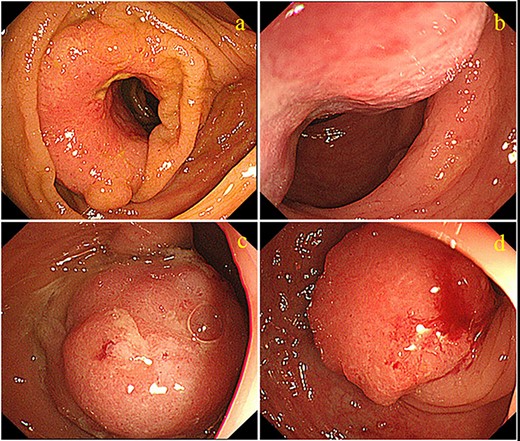

A 70-year-old man who was positive for a blood stool test visited our hospital. Colonoscopy, computed tomography (CT) and barium enema indicated quadruple concurrent locally advanced cancers. The first tumor, with observed lumen stenosis, was located in the ascending colon; the second tumor was located in the descending colon and the third and fourth tumors were located in the sigmoid colon (Fig. 1). CT revealed marked intestinal wall thickness in the ascending, descending and sigmoid colon (Fig. 2). Preoperative precise simulation using 3D angiography was performed to determine adequate lymph node dissection along the arteries feeding the tumors and appropriate resection to avoid anastomotic leakages.

Abdominal CT scan revealing a tumor of the ascending colon (a, arrowhead). A tumor in the descending colon (b, arrowhead), and two tumors in the sigmoid colon are also visible (c, d, arrowhead)